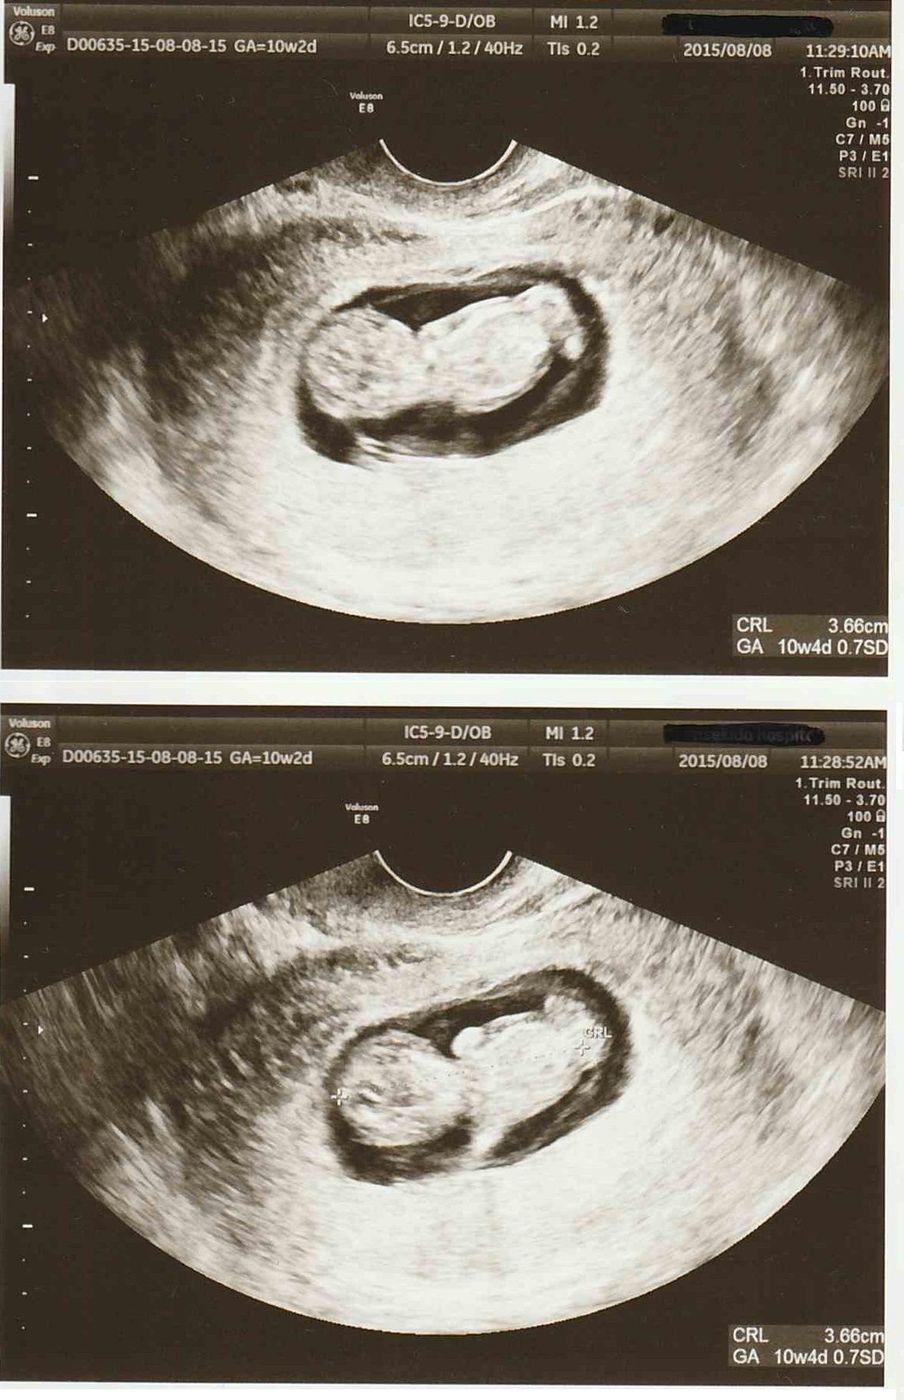

テーマ: ふー妊娠6ヶ月~7ヶ月* 先週の金曜日に初 4Dエコー に行ってきました ウチの病院は4Dはいつもの先生じゃなくって、 専任の技師さんが担当してくれるのですが、 予約が平日の午後しかなくって、ダンナと休暇エコーの写真だけでなく4dもやってる病院で、健診がすごく楽しみでした。 顔がエコーに映っていないと、写真はもらえませんでした。 果たして胎児は男の子なのか、女の子なのか。エコーでいつ、どんなふうに性別がわかるの? オービス 1 :名無しさん:(日) IDd//URnS5net って、速度超過で通り過ぎても、稼働しない場合があるん

#25weekpregnant #7monthpregnant #babygirl #4dエコー 16週0日(16w0d・女の子)|ちーーさん さん(26歳) エコー写真撮影時のエピソード: なかなか顔を見せてくれず常に足か手で顔隠してたんですが、この時やっと顔見せてくれて主人とどっち似かね~って話したりしました。 義母は、「最近のエコー写真凄いね。初めての4Dエコー鮮明さにびっくり! うちは男男女と上に3人子供が居て、4人目は娘の遊び相手になってくれたらと女の子を希望しているので、性別が分かるのがドキドキです! 横顔が笑ってるように見えてとってもかわいいです♡ 腕を顔の前で交差